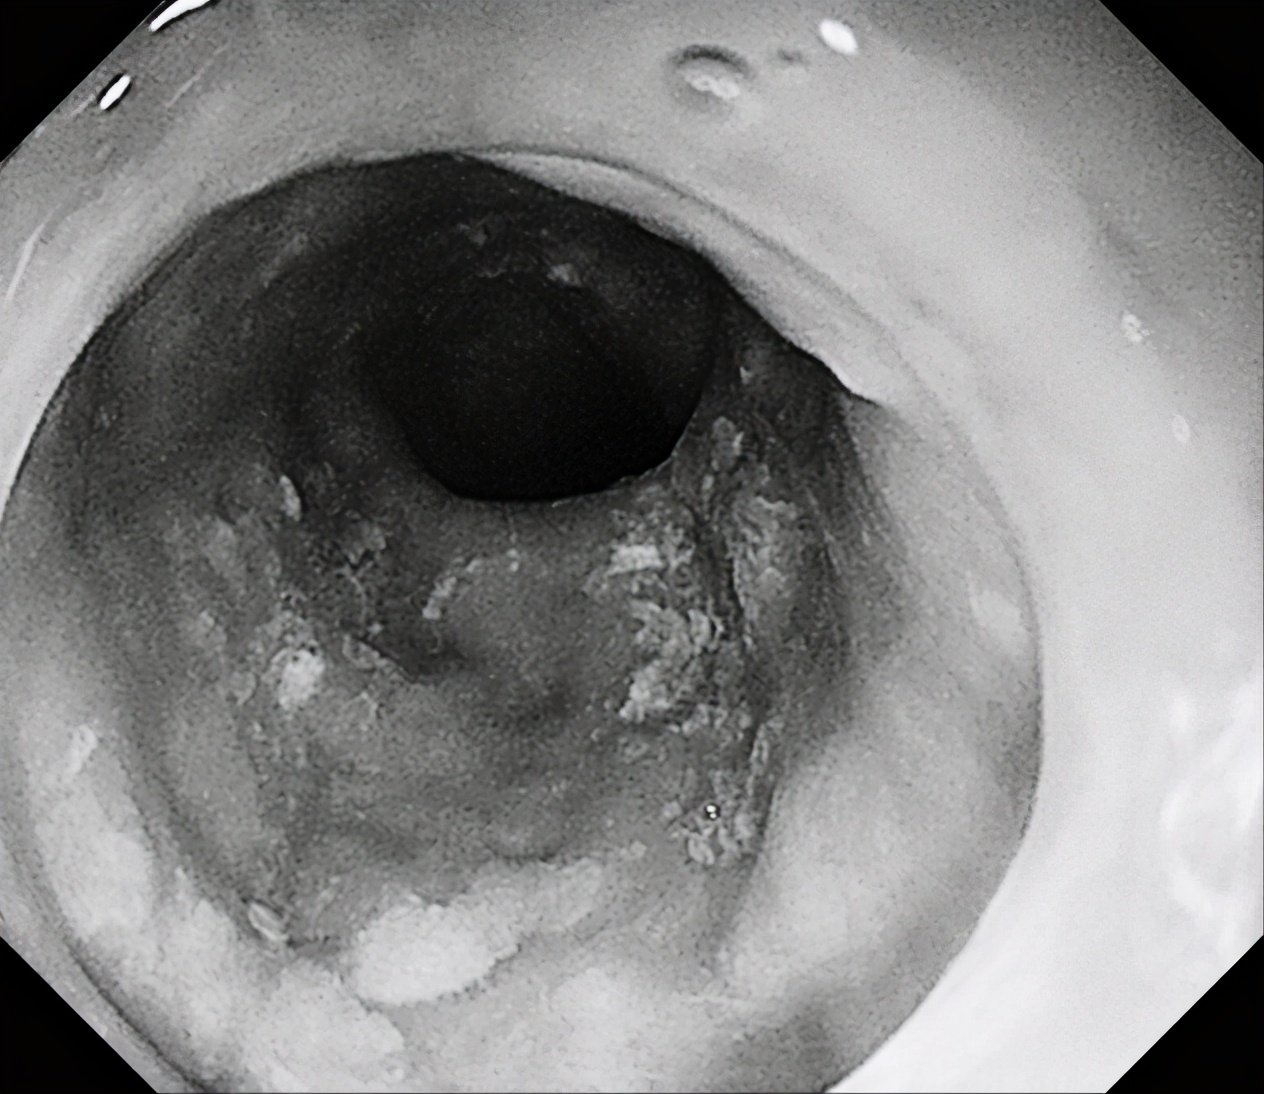

1月6日下午,消化内镜中心张蓉副主任医师为一名患者行胃镜检查时,发现食管中下段黏膜粗糙,覆不均匀少许白苔,粘膜微血管增粗紊乱,行NBI观察及卢戈氏碘染色后发现患者病变呈全周型。